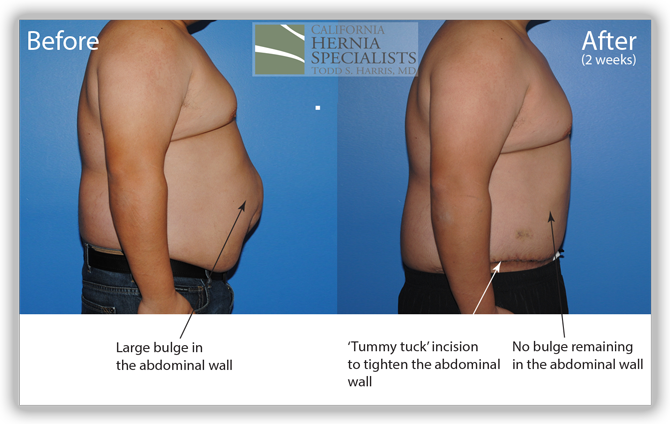

A ‘tummy tuck’ incision was used to help tighten and remove excess skin and the old scar. The old mesh had completely separated from the muscle and was stuck to the small intestines internally. Careful removal of the mesh was required to free the intestine from the hernia. The muscle was closed and a new piece of advanced mesh was placed under the muscle to reinforce the repair. The images below are from before and after his hernia surgery.

In the images below we compare the pre-operative photos to the post-operative photos taken just 2 weeks after his surgery.

The patient continued to lose weight after his surgery. He was followed for 6 months and did very well throughout this time returning to normal activities after about 4-6 weeks.